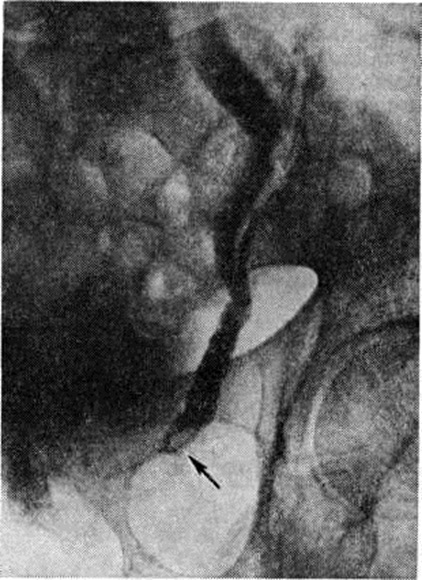

Рентгенологические метод является основным в диагностике Почечнокаменная болезнь Он позволяет выявить не только наличие камней, но и установить их форму, величину, локализацию, структуру, а также получить представление об изменениях в анатомо-функциональном состоянии почек и мочевых путей. Исследование начинают с обзорной рентгенографии брюшной полости, начиная от ThXl до лонного сочленения. Обнаружение на обзорной рентгенограмме тени, подозрительной на конкремент, не требует дифференциальной диагностики только в случае коралловидного камня, являющегося слепком чашечно-лоханочной системы (рисунок 2). Камни почечных чашечек представляют собой их слепки или имеют неправильную, округлую форму; камни почечной лоханки часто округлые или треугольные; камни мочеточника — цилиндрической, веретенообразной или неправильной формы. При аномалиях мочевых путей конкремент может находиться вне обычной локализации почек и других органов мочеполовой системы. Обнаружение камня на снимке зависит от его размеров, химический состава и локализации. Наиболее интенсивное изображение дают оксалаты, затем камни смешанного состава и фосфаты. Оксалаты имеют шиповидные, фестончатые контуры и напоминают тутовую ягоду. Коралловидные камни чаще всего компактны, но могут быть слоистыми, как и остальные конкременты смешанного состава, иногда они достигают гигантских размеров. Слоистое строение камней на рентгенограммах обусловлено различной проницаемостью для рентгеновского излучения составляющих их солей. Около 10% камней с низким атомным весом (ураты, белковые, цистиновые и ксантиновые камни) не видны или дают неотчётливую тень. Особенно трудно выявить камни, проецирующиеся на костный скелет (ребра, поперечные отростки позвонков, крестцово-подвздошные сочленения). Для их обнаружения производят прицельные снимки в косых и атипичных проекциях, томо или зонографию. Томография (смотри полный свод знаний), применяемая самостоятельно или в сочетании с контрастными исследованиями, показана при недостаточной подготовке больного к рентгенологическое исследованиям, почечной колике, сопровождающейся парезом кишечника, или при малых размерах камней. Поскольку при Почечнокаменная болезнь довольно часто конкременты самопроизвольно отходят из чашечно-лоханочной системы, они могут проецироваться по ходу мочеточника паравертебрально, имеют тенденцию задерживаться над одним из его анатомических сужений. Наиболее важные сведения о принадлежности выявленной тени к мочевым путям, о локализации камня, вызванных им нарушениях функции почек, уродинамики, анатомического состояния мочевых путей (гидрокаликоз, пиелэктазия, гидроуретеронефроз — расширение чашечек, лоханки, мочеточника и почки) выявляются при экскреторной урографии (рисунок 3, б) с предварительной обзорной рентгенографией (рисунок 3, а). Она позволяет установить вид лоханки (открытая или закрытая, внутрипочечная или внепочечная), состояние лоханочно-мочеточникового сегмента (смотри полный свод знаний: Пиелография). Обычно рентгенопозитивный конкремент определяется в мочевых путях, но иногда его изображение перекрывается, как бы тонет на фоне контрастированной мочи, особенно при небольшом камне или малой интенсивности его изображения. При рентгенонегативных камнях виден дефект наполнения мочевых путей (в том числе и лоханки) с чёткими контурами (рисунок 4). В отличие от опухоли лоханки в косых проекциях вокруг камня сохраняется ободок контрастного вещества. Обычно при камнях лоханки, достигающих в диаметре 3 сантиметров и более, наблюдаются пиелэктазия и гидрокаликоз. Произведённые в процессе экскреторной урографии телевизионная пиелоуретероскопия в сочетании с кинематографией или видеомагнитофонной записью изображения позволяют оценить нарушения тонуса и моторной функции верхних мочевых путей при камнях, отличить спастические, функциональный процессы от органических. Если спустившийся в мочеточник камень частично закрывает его, то отмечаются расширение мочеточника и лоханки (пиелоуретерэктазия) выше уровня расположения конкремента. На экскреторных урограммах, произведённых во время почечной колики, выявляется увеличенная почка с усиленным нефрографическим эффектом без контрастирования чашечно-лоханочной системы и мочеточника — так называемый большая белая почка. Такая рентгенологическое картина указывает, что функция почки сохранена. При длительной полной блокаде камнем (более 3—4 недель) функция почки из-за атрофии снижается и может полностью утрачиваться. На экскреторных урограммах, произведённых после почечной колики, иногда наблюдается проникновение контрастированной мочи за пределы мочевых путей, а также лоханочно-почечный рефлюкс. Ретроградную пиелоуретерографию с жидким контрастным веществом или кислородом производят только при значительном снижении функции почек, при сомнении в диагнозе, особенно в тех случаях, когда при экскреторной урографии не выявляется рентгенонегативный камень. Рентгенографию мочеточника после введения в него катетера производят в прямой и косой проекциях. Если при этом тень, подозрительная на камень, на обоих снимках находится рядом с катетером или сливается с его тенью, то диагноз Почечнокаменная болезнь не вызывает сомнений. Тень, не относящаяся к мочеточнику, определяется на некотором расстоянии от катетера. На ретроградных пиелограммах с жидким контрастным веществом небольшой концентрации рентгенонегативные камни выявляются в виде дефекта наполнения. Особенно демонстративными такие камни становятся при пневмопиелорентгенографии или пневмопиелотомографии (рисунок 5). С помощью ретроградной уретерографии удаётся выявить рентгенонегативный камень в мочеточнике, верхние границы дефекта при этом имеют вогнутую форму (рисунок 6).